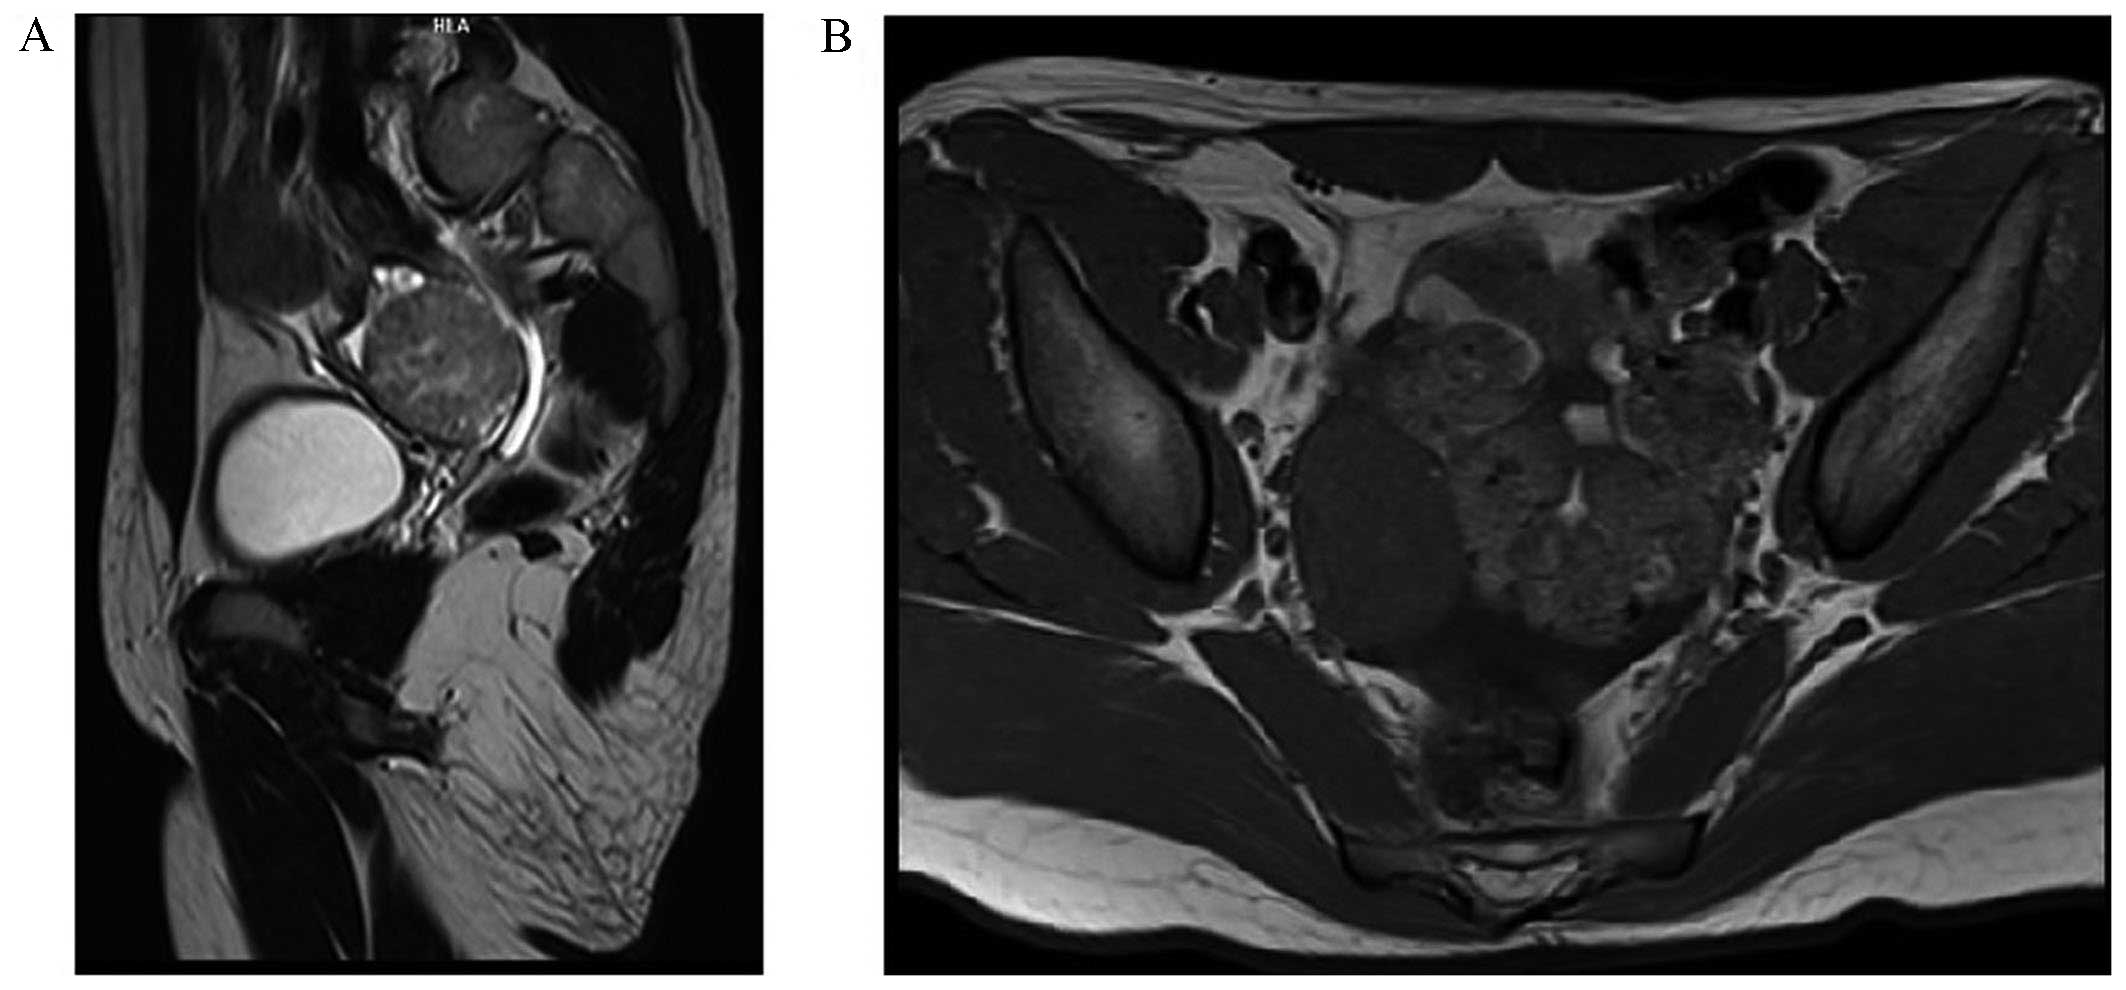

Laboratory findings revealed an elevated plasma total testosterone level of 8.84 nmol/l (normal: 0.17–2.81 nmol/l). The serum levels of dehydroepiandrosterone sulfate, follicle-stimulating hormone, luteinizing hormone, estradiol, progesterone, thyroid-stimulating hormone, prolactin, α-fetoprotein (AFP), cancer antigen-125 and cancer antigen-15-3 were within normal limits. A pelvic ultrasonography revealed a well-defined heterogeneous mass of 12×12 mm within the right ovary measuring 23×16 mm; other findings were normal. Pelvic, retroperitoneal and renal magnetic resonance imaging analyses made with a Siemens Magnetom Avanto™ MRI scanner demonstrated the presence of a solid lesion in the right ovary of 36×42×45 mm, minor grade hepatosplenomegaly and ascites (Fig. 1). The patient underwent laparoscopic surgery, during which a right-ovarian tumorous mass of 5×4 cm with abnormal vascularization was encountered. The right and left Fallopian tubes, the left ovary and the uterus appeared to be normal. A right ovarian oophorectomy was performed with a LigaSure™ device (5 mm blunt tip, ForceTriad™ energy platform; Covidien-Medtronic, Minneapolis, MN, USA), and the mass was removed in an Endobag™ (ASID BONZ GmbH, Herrenberg, Germany) to avoid spreading of the cancer cells.

Figure 1.

Magnetic resonance imaging findings. (A) T2-weighted MRI of the abdomen (sagittal view) with hyperintense solid laesion in the right ovary. (B) In the T1-weighted image (axial view), the mass is hypointense.